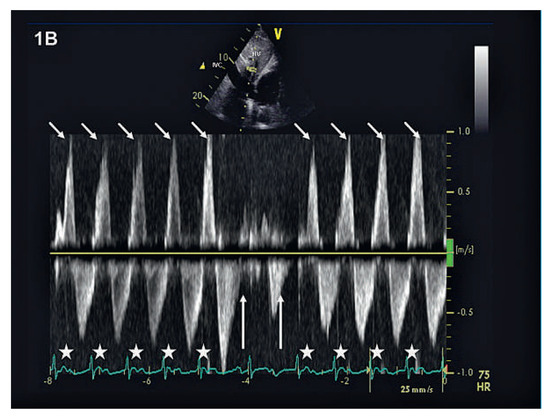

We report on the worldwide first implantation of a transcatheter valve in mitral position using a surgical approach to treat severe combined mitral valve disease, complicated by massive calcifications of the whole mitral anulus. The management of suc...